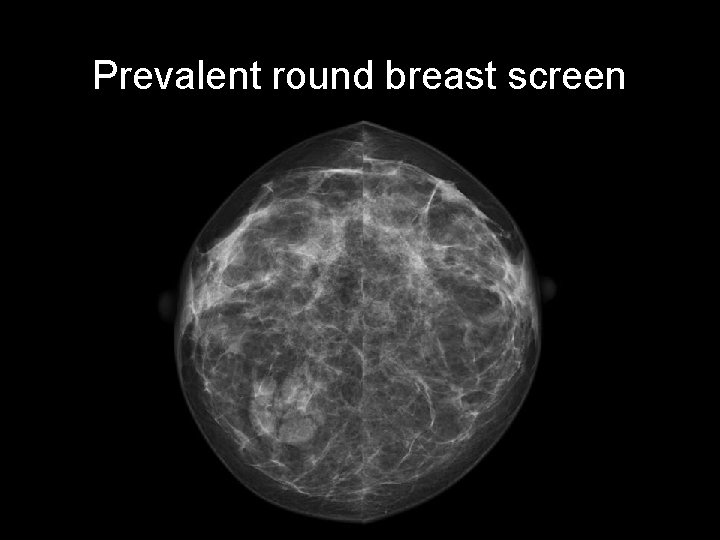

Prevalent round breast screen CASE 5 • • Prevalent round breast screen. Asymptomatic. Age: 41 years old Gender: Female Race: Caucasian • First study? – Ultrasound – Mammography – MRI w contrast

Prevalent round breast screen

Prevalent round breast screen • Round lobulated right breast mass with sharp outline and halo • Lucent lines within the mass due to air within the lesion SKIN LESION: NAEVUS http: //radiopaedia. org/cases/breast-naevus